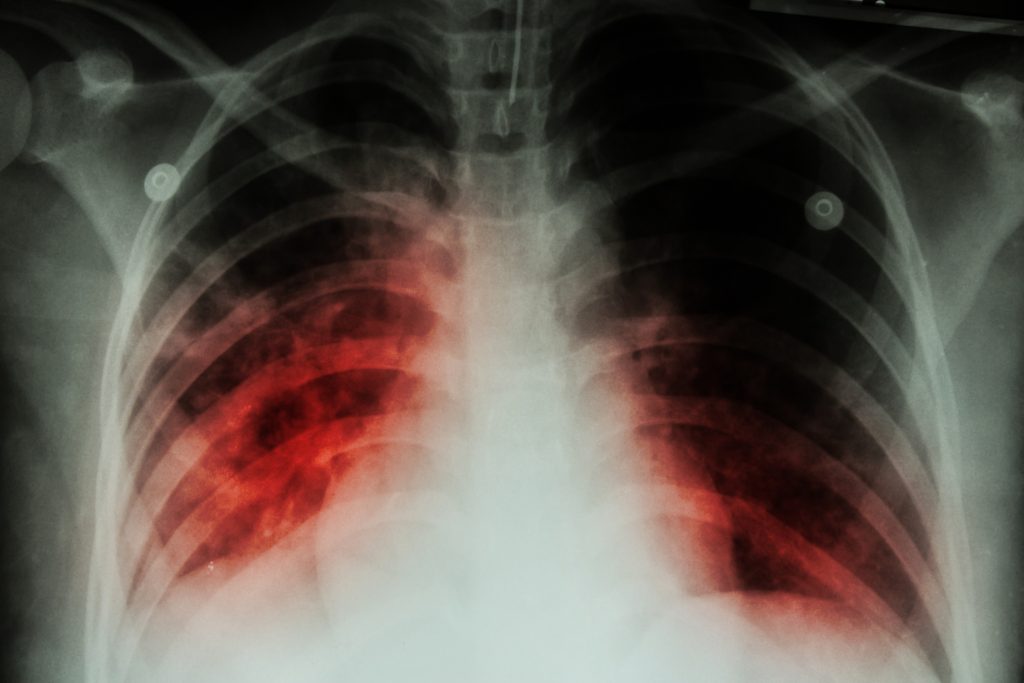

Can Hiv Cause Lung Infection . This lung infection spreads through the air when someone with active tb coughs, sneezes, or talks. Lungs are the most commonly involved organ by hiv/aids related diseases, and pulmonary infections are the main reasons for the. Increasing emphasis should be placed upon prevention of infection. Since the 1980s, pneumocystis pneumonia, or pcp, has infected thousands of hiv/aids patients. It’s common in people with advanced or. Immunosuppression associated with human immunodeficiency virus (hiv) infection impacts all components of host defense. Bacterial pulmonary infections occur commonly in people with human immunodeficiency virus (hiv) [1]. Bacterial pneumonia with typical infectious organisms (streptococcus pneumoniae, haemophilus, pseudomonas, staph species,.

Bacterial pulmonary infections occur commonly in people with human immunodeficiency virus (hiv) [1]. Since the 1980s, pneumocystis pneumonia, or pcp, has infected thousands of hiv/aids patients. Immunosuppression associated with human immunodeficiency virus (hiv) infection impacts all components of host defense. Bacterial pneumonia with typical infectious organisms (streptococcus pneumoniae, haemophilus, pseudomonas, staph species,. Lungs are the most commonly involved organ by hiv/aids related diseases, and pulmonary infections are the main reasons for the. Increasing emphasis should be placed upon prevention of infection. It’s common in people with advanced or. This lung infection spreads through the air when someone with active tb coughs, sneezes, or talks.